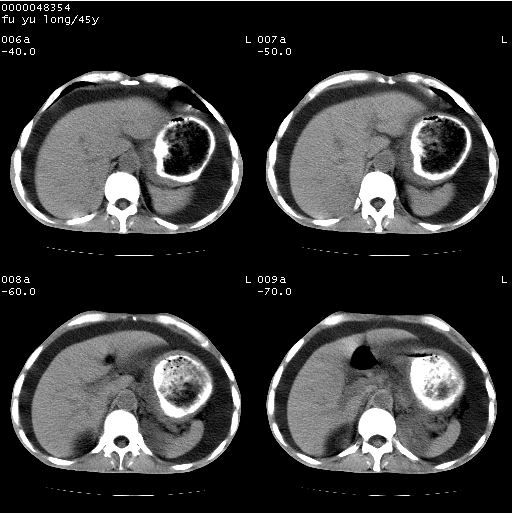

以下是引用lkc8963在2008-5-30 8:44:00的发言:[br]胃窦癌伴网膜(胃结肠韧带)/腹膜及腹膜后淋巴结转移.

以下是引用医影拾贝在2008-5-30 2:38:00的发言:[br]气肿性胃炎、胃十二指肠溃疡、腹膜炎,考虑穿孔可能性较大